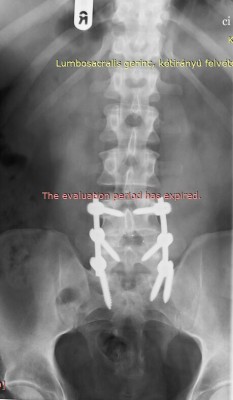

Miskolcon,Demeter főorvos úr műtötte.Gerinc stabilizálás+2 sérv.(csavarok és fémrudak,távtartó).

hello mindenkinek,11.09.-én megműtötték a férjemet.Túl vagyunk tehát rajta!!!Minden nap jobban van,de az első 3-4 nap pokol volt.Most a járást gyakorolja gerincfűzőben,egész jól megy!

Sziasztok!A helyzet nem jó,sőt rossz!Most voltunk CT-n,a sérv ki van szakadva,ráadásul ott van ahol a szétcsúszás is van.A lehető legrosszabb minden ,a tartó szalagok is el vannak szakadva.Az idegsebész szerint kb. 4 órás műtét.Járni még tud.A doki azt mondta,hogy a műtét biztos csak idő kérdése.Arra gondoltunk ,jó lenne még1 orvos véleménye is .Pl.:milyen anyagokkal hogyan történne a műtét.Kérek mindenkit,hogy aki Debrecenben,vagy B.pesten,Miskolcon tud spec.orvost,Írja meg!!Köszönöm.Nagyon meg vagyunk ijedve,fogalmunk sincs,hogyan tovább...........